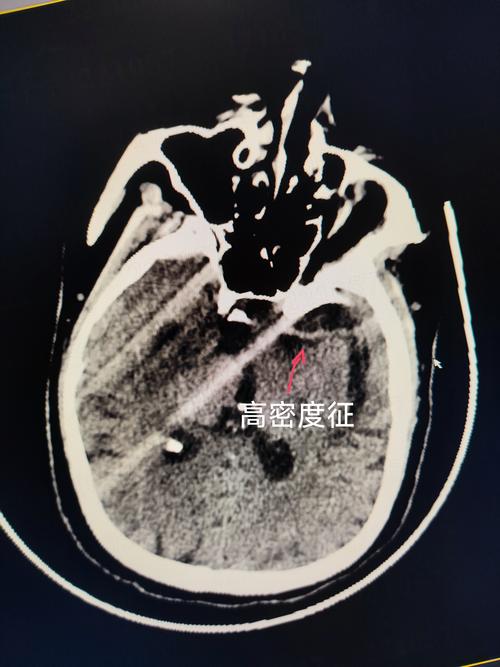

(图片来源网络,侵删)

(图片来源网络,侵删)